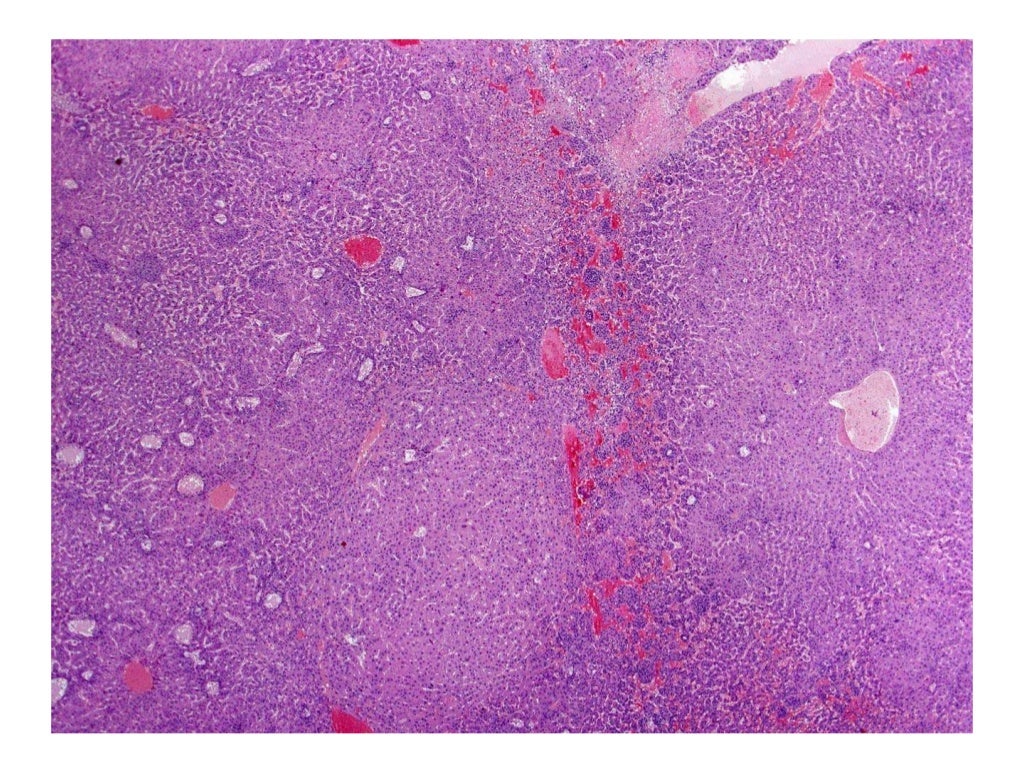

이번 공부거리는 Focus on Tox Path에 게시된 Xenonbiotic 유도 간 독성 병리에 관한 슬라이드 강의입니다.

출처: https://focusontoxpath.com/xenobiotic-induced-toxicologic-pathology-ofthe-liver/